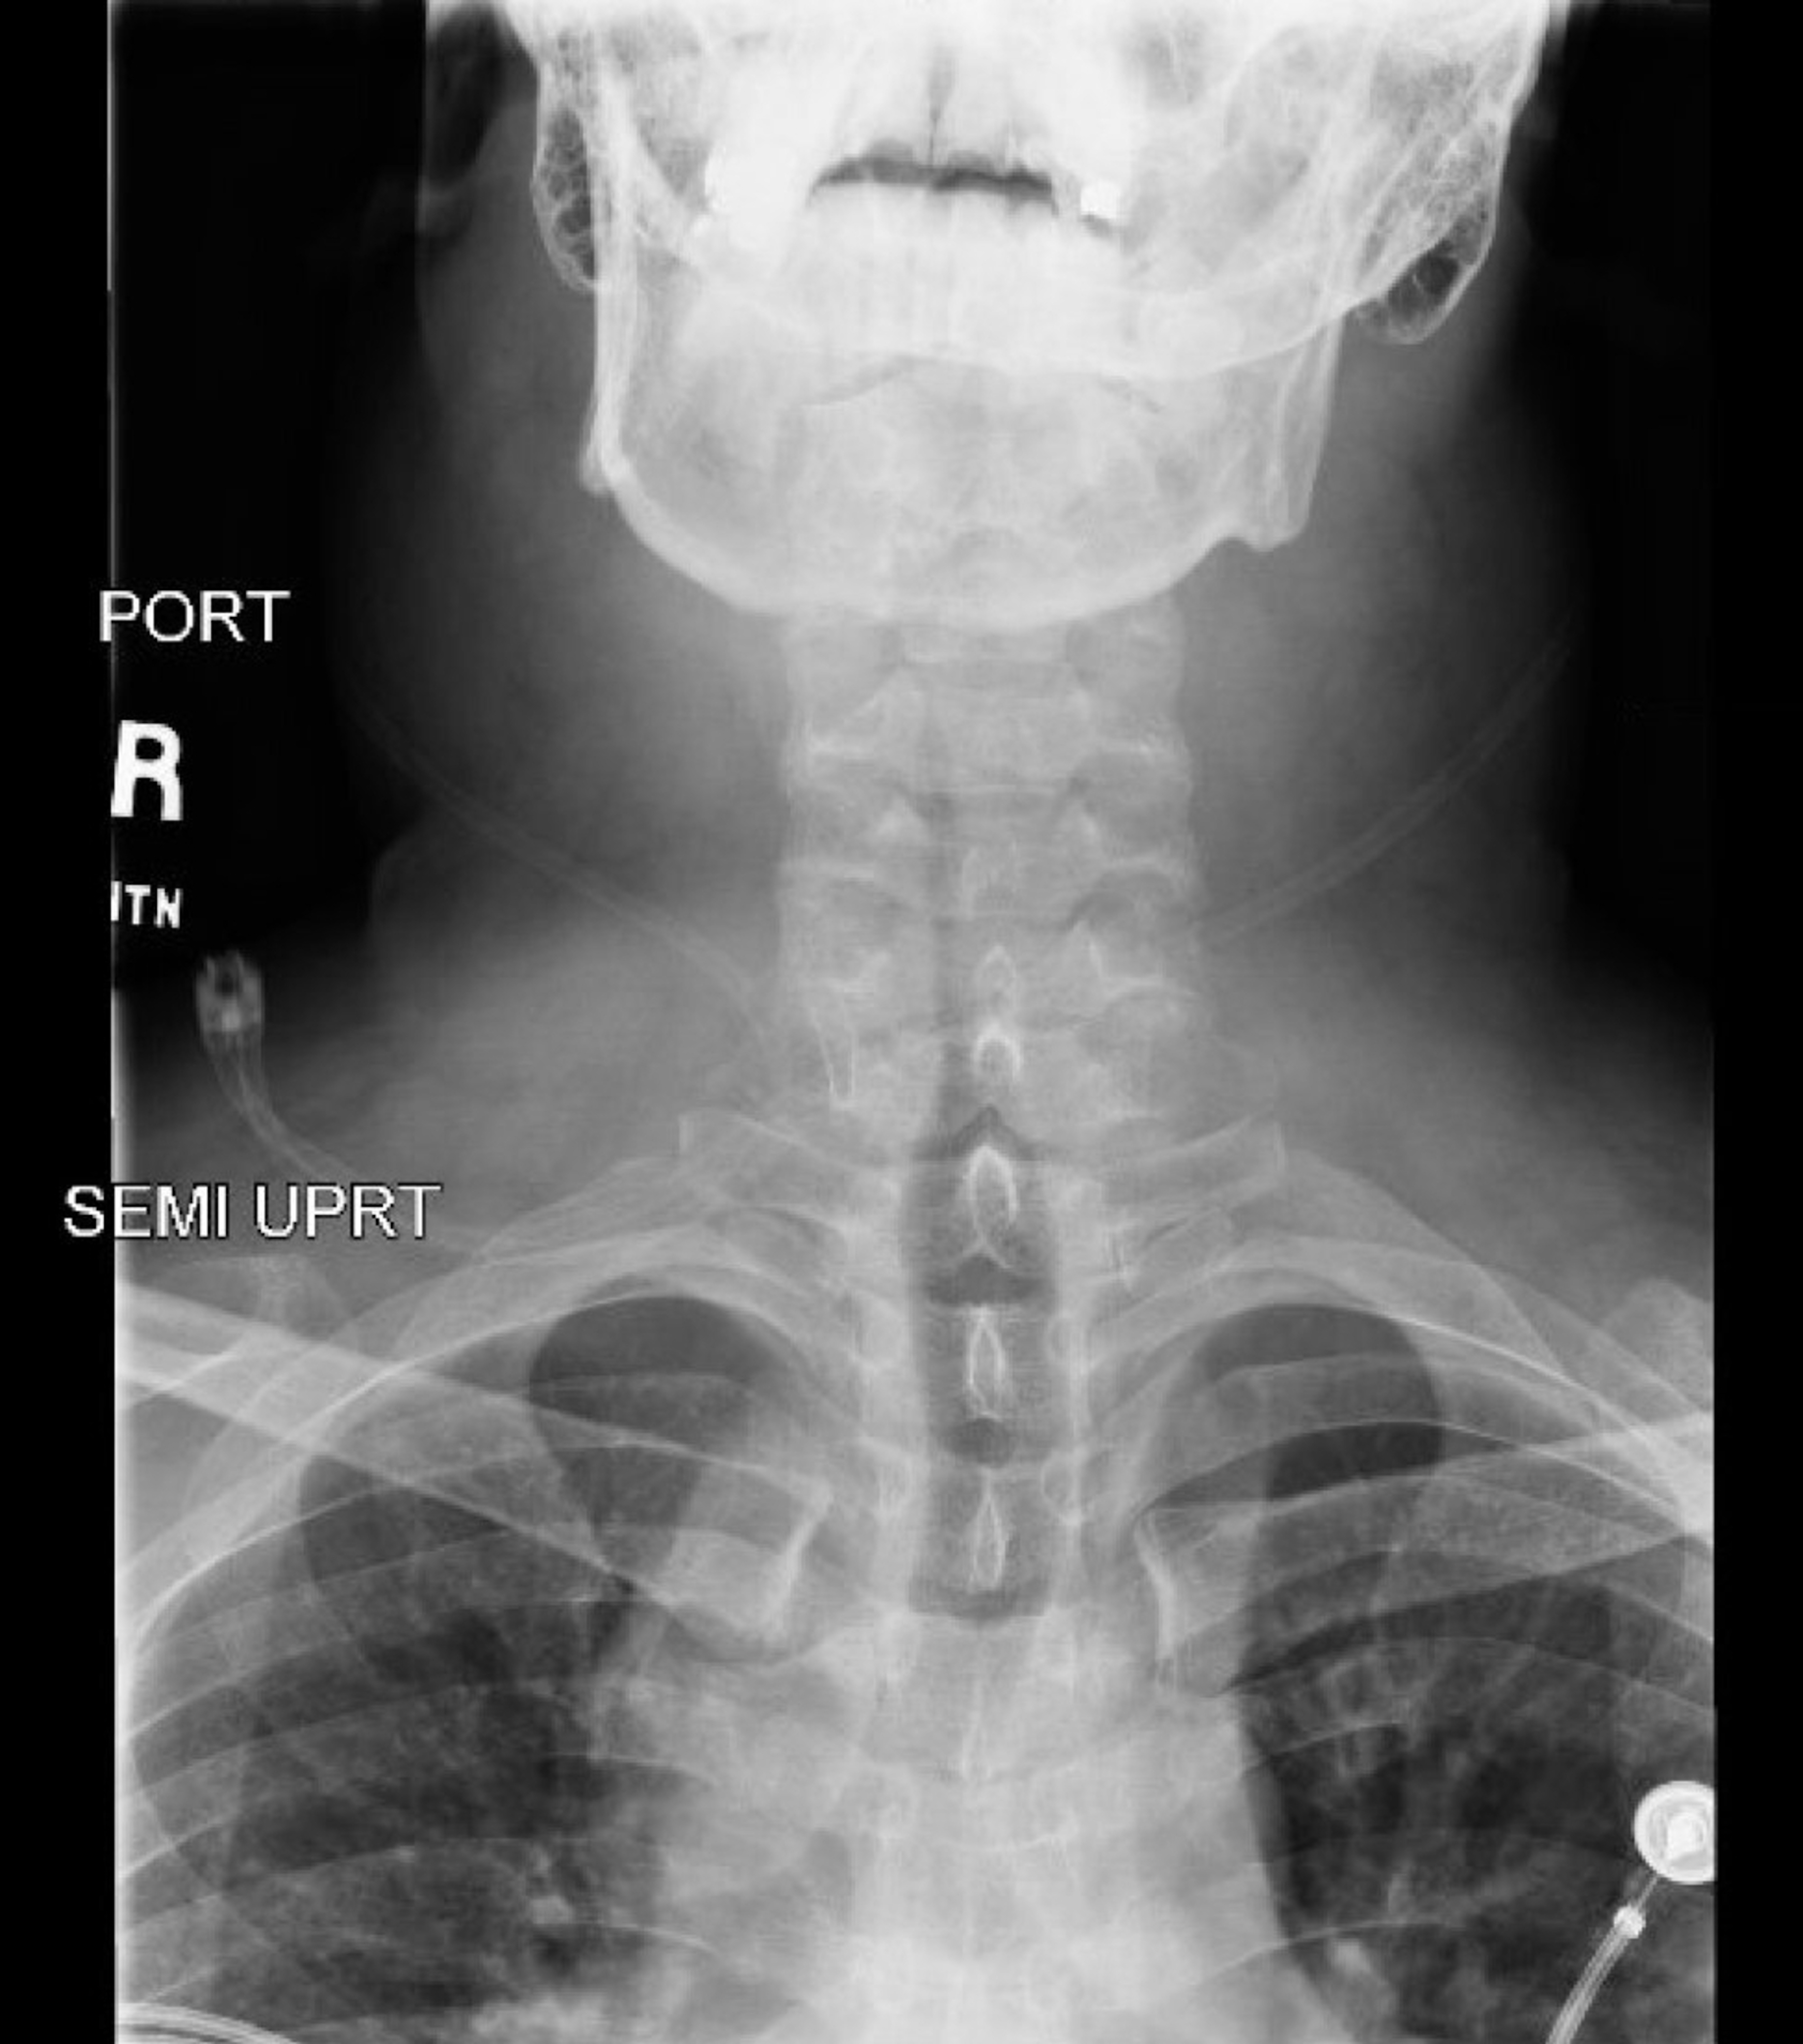

Airway Narrowing Associated with Hodgkin’s Lymphoma AP XR Unannotated. JETem 2020